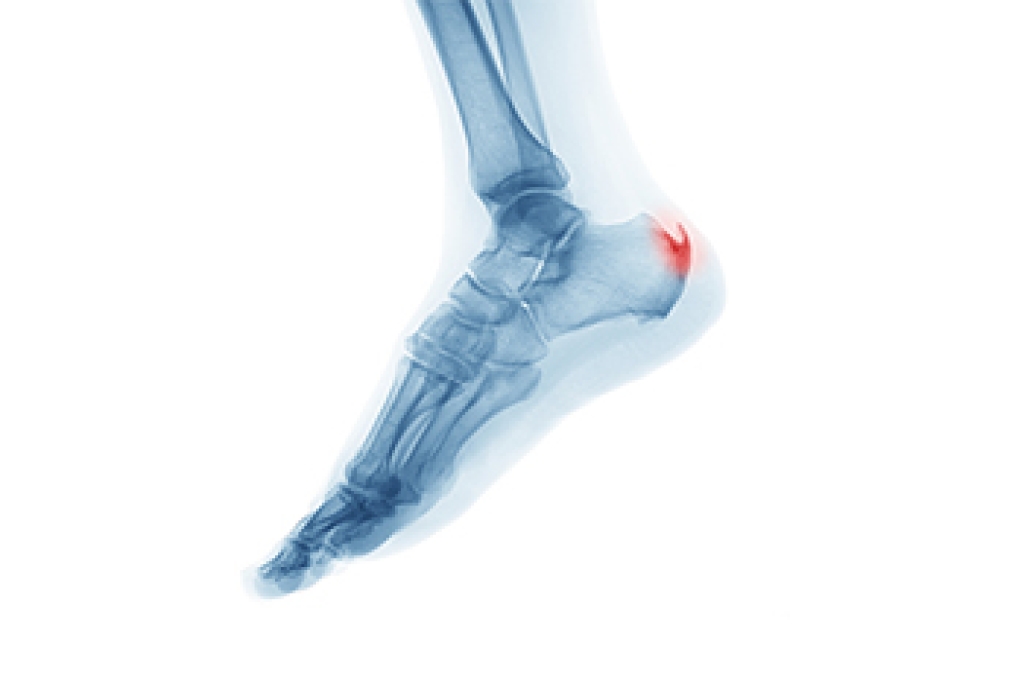

A broken foot, though painful and distressing, is a relatively common injury that can result from various causes. One of the primary causes of a broken foot is trauma. This can occur from accidents such as falls, sports injuries, or motor vehicle collisions. A sudden and forceful impact can fracture one or more bones in the foot. Treatment for a broken foot typically involves immobilization, often with a cast or splint, to allow the bones to heal properly. In some cases, surgery may be necessary to realign and stabilize the broken bones. Pain management may be necessary in the recovery process. Understanding the causes and seeking prompt medical attention is essential when dealing with a broken foot. With the right treatment, individuals can expect a full recovery and a return to their normal activities. If you have endured a broken foot, it is suggested that you confer with a chiropodist as quickly as possible who can guide you toward the treatment that is right for you.

A foot fracture is a crack or break in a foot bone, often caused by repetitive stress on the foot or a high-impact foot injury. If you’re suffering from foot pain, please consult with one of the specialists from Thornhill Foot Clinic. Our chiropodists can help you maintain the health of your lower limbs and your mobility.